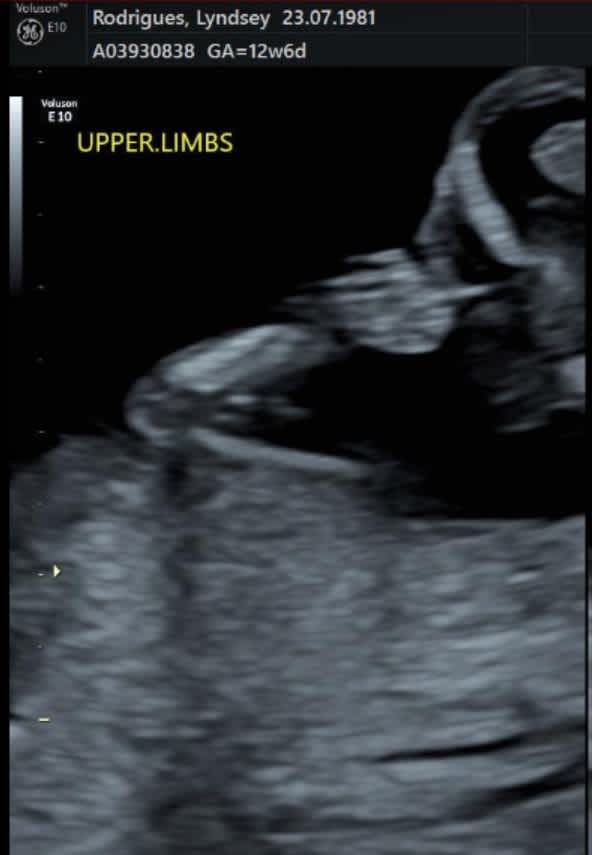

At 13 weeks, I went for another scan and there was my kid, two arms, two legs, two sides of their brain and the cutest little tush you ever did see. As the ultrasound technician panned the camera I burst out laughing.

“They’re giving me the finger!”, I exclaimed, a rush of pride and affection flooding toward this sassy little miracle in my belly.

Yes, this kid has obviously inherited my attitude (lord, help me) but they have also clearly inherited their father’s ability to swiftly assuage any and all of my fears because, at that moment, I knew our life could never be boring. I realised that who I am doesn’t have to completely change with motherhood. I’m still going to be me, I’m just going to have one more amazing person to share my adventures with.

I plan to frame that ultrasound photo of our baby flipping me the bird and hang it in their nursery because not only does it make me laugh, but when I look at it, I’m reminded that the best adventures in life will always be worth waiting for — and I am so glad I waited for this one.